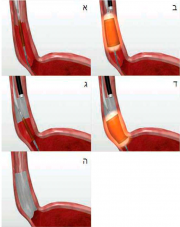

| 12:09, 30 במאי 2013 | EndoBarrier2.png (קובץ) |  |

219 קילו־בייטים | Motyk | 1 | |

| 09:47, 30 במאי 2013 | EndoBarrier1.png (קובץ) |  |

125 קילו־בייטים | Motyk | 1 | |

| 09:51, 29 במאי 2013 | וועב6.png (קובץ) |  |

383 קילו־בייטים | Motyk | 1 | |

| 12:25, 28 במאי 2013 | ועב5.png (קובץ) |  |

281 קילו־בייטים | Motyk | 1 | |

| 12:16, 28 במאי 2013 | ועב4.png (קובץ) |  |

257 קילו־בייטים | Motyk | 1 | |